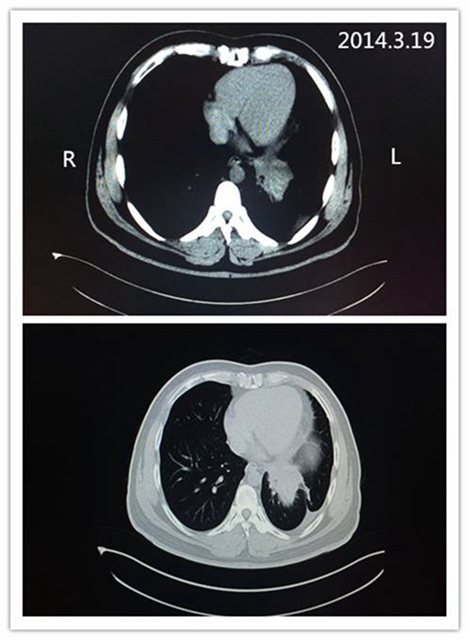

治疗中期的CT影像: